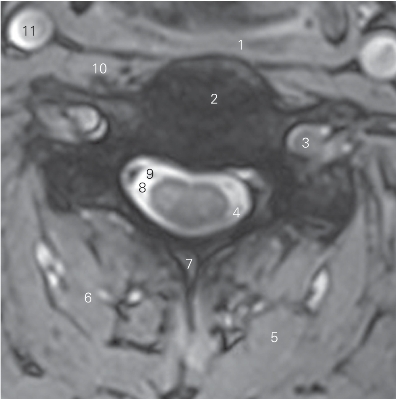

图1-4 经第4颈椎间盘的横断层MR T2加权图像

1 咽下缩肌 inferior constrictor of pharynx

2 第4颈椎间盘 4th cervical vertebral disc

3 椎动脉 vertebral artery

4 脊神经后根 posterior root of spinal nerve

5 头半棘肌 semispinal capitis 6 颈半棘肌 semispinal cervicis

7 棘突 spinous process 8 蛛网膜下隙 subarachnoid space

9 脊神经前根 anterior root of spinal nerve

10 颈长肌 longus colli

11 甲状软骨上角 superior cornu of thyroid cartilage